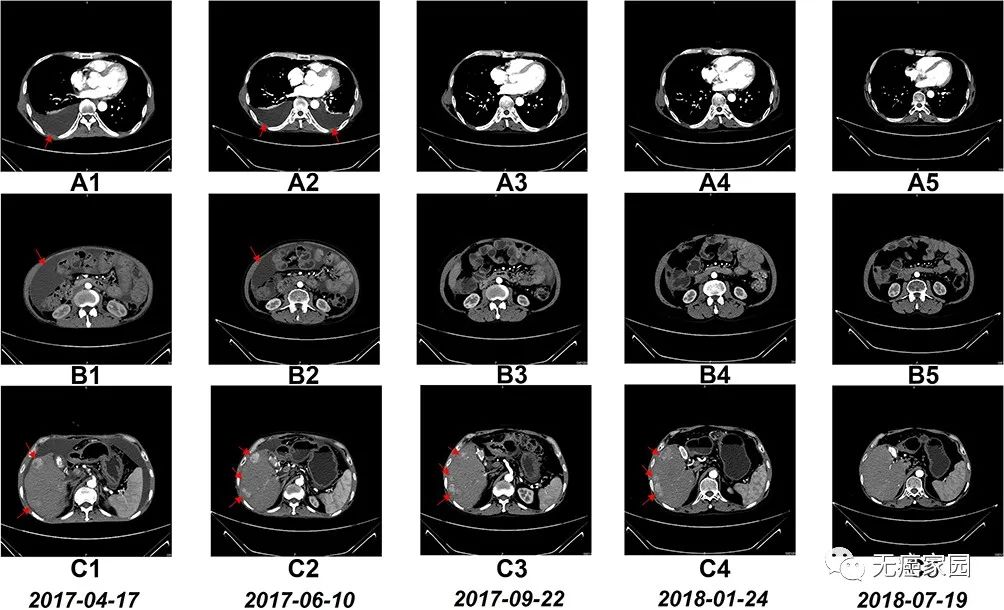

研究人员在NK细胞治疗前后进行了计算机断层扫描 (CT),以进行基于影像学的诊断,并评估临床效率。

6个疗程后,患者的胸水和腹水明显减少。自治疗结束以来,患者一直保持这种状态。此外,在NK细胞治疗17个疗程后,右肝叶中的多个肿瘤体积减小。

NK细胞治疗前和治疗期间的CT扫描结果

图A1~A5:CT扫描显示,6个疗程后胸腔积液完全消失;

图B1~B5:CT扫描显示,6个疗程后腹水几乎完全消失;

图C1~C5:CT:扫描显示,肝右叶多个肿瘤的大小在17 个疗程后显著缩小;